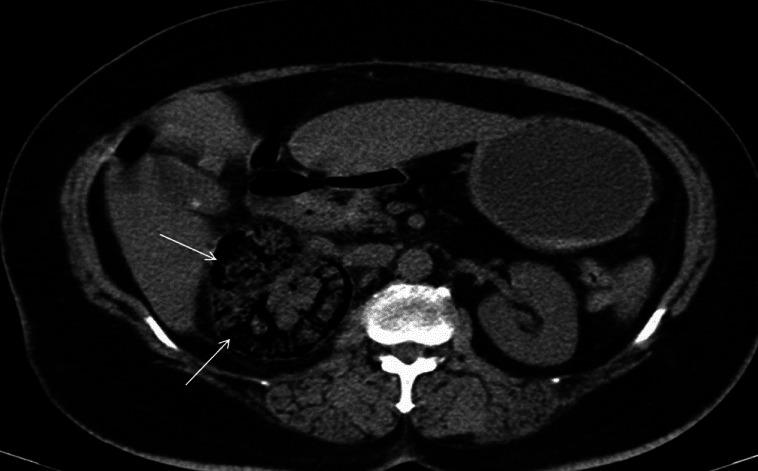

We present our experience of 22 cases of emphysematous pyelonephritis (EPN) treated from 1996 to 2012. Medical records were analyzed retrospectively for demographic profile, presence and duration of diabetes mellitus, and mode of clinical presentation. EPN was diagnosed based on demonstration of intra-renal gas by plain X-ray, ultrasound, and/or computed tomography (CT) scan. Details of medical treatment, reason for surgical intervention, and final outcome were recorded. Univariate analysis was performed to identify risk factors for mortality and P value of less than 0.05 was taken as significant. Twenty-two cases (6 males, 16 females) of EPN were diagnosed. Seven cases presented with acute pyelonephritis, seven cases with urosepsis, and the remaining eight patients with multi-organ dysfunction. CT grading of EPN was class IV in three, class III in four, class II in 14, and class I in one. All were initially managed medically with parenteral antibiotics. Ten patients needed additional surgical intervention. The overall survival rate was 86.3% (19/22). Among the risk factors analyzed higher CT grade, altered sensorium and thrombocytopenia were significantly associated with mortality. We conclude that a more conservative approach in managing EPN has become the standard of care. Patients having high CT grade of lesions (III and IV) with altered sensorium and thrombocytopenia at presentation are more likely to die due to the disease and may be better managed by an aggressive surgical plan.